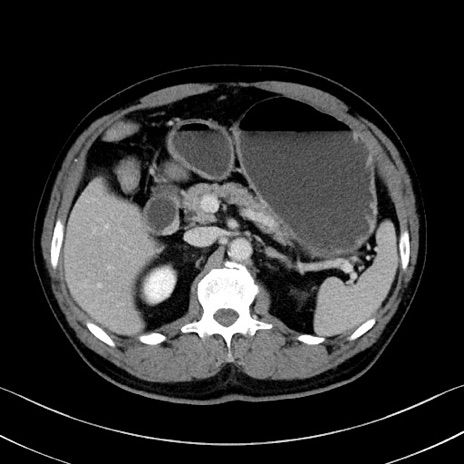

症例35(横断像)

【症例】70歳代 男性

【主訴】腹部膨満、嘔吐

【現病歴】昨日より腹部膨満感出現。本日増悪し、仙痛出現。嘔吐あり、受診。

【既往歴】糖尿病、胆摘後

【身体所見】BP 149/80mmHg、HR 74/min、BT 35.9℃、腹部:膨満、軟、圧痛なし。腸雑音減弱あり。上腹部正中切開瘢痕あり。

【データ】WBC 13500、CRP 1.72